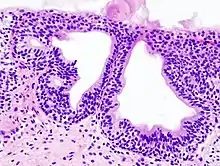

Cystitis glandularis at trigone

Cystitis glandularis is the transformation of mucosal cells lining the urinary bladder. They undergo glandular metaplasia, a process in which irritated tissues take on a different form, in this case that of a gland.[1] The main importance is in the findings of test results, in this case histopathology. They must distinguish a benign metaplastic change from the cancerous condition urothelial cell carcinoma.[2] It is a very common finding in bladder biopsies and cystectomies, and most often found in the trigone area. Cystitis glandularis lesions are usually present as small microscopic foci; however, occasionally it can form raised intramucosal or polypoid lesions. The cystitis glandularis lesions are within the submucosa.

Cystitis glandularis arises from and merges with Von Brunn's nests, which are groups of urothelial cells (cells of urinary tract) within the lamina propria and submucosa, formed from budding from the surface mucosa. They are considered normal. Cystitis cystica is a similar lesion to cystitis glandularis, where the central area of the Von Brunn's nests have degenerated, leaving cystic lesions. Other metaplastic entities in the urinary bladder include squamous metaplasia and nephrogenic adenoma.